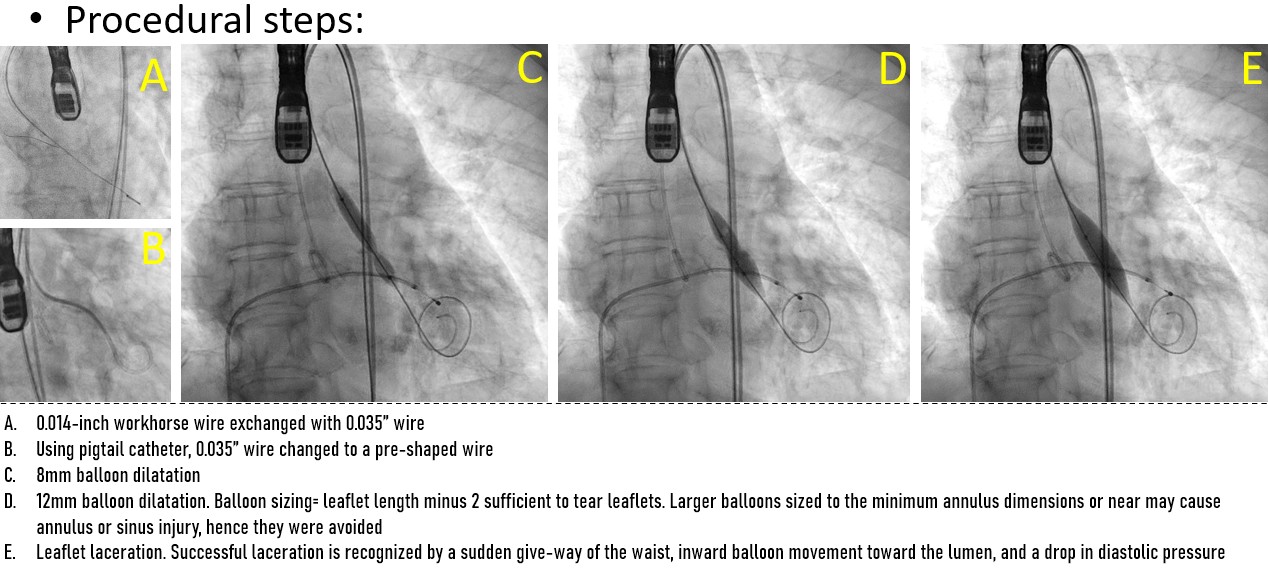

A controlled laceration of the native left coronary cusp was planned under general anaesthesia. A puncture point 2 mm above the cusp base, aligned with the coronary ostium, was selected to ensure optimal leaflet splay and minimise recoil risk following laceration. Leaflet traversal was performed using electrocautery at 50 W in pure-cut mode, delivered through a 0.014-inch, 300-cm Astato wire (ASAHI) advanced via a 150-cm Finecross microcatheter (Terumo), housed within a 6-French, 125-cm multipurpose diagnostic catheter and an 8-French Amplatz Left guide catheter. After advancing the microcatheter into the left ventricle, the Astato wire was exchanged for a 0.014-inch Fielder wire. Initial dilatation was performed using a 3 mm non-compliant Apollo balloon (BrosMed Medical). The Fielder wire was then exchanged for a 0.035-inch, 260-cm J-tip wire, and subsequently for a pre-shaped Safari wire (Boston Scientific). Based on procedural planning, a balloon size equal to or up to 2 mm shorter than the leaflet length was deemed adequate to achieve effective laceration while avoiding sinus or annular injury. Controlled leaflet laceration was performed using sequential balloon dilatations with an 8-mm Armada balloon (Abbott Cardiovascular) followed by a 12-mm Mustang balloon (Boston Scientific). Successful laceration was indicated by a sudden give-way of the balloon waist, inward balloon shift toward the lumen, and a drop in diastolic pressure. A balloon-expandable valve was implanted.

•Controlled leaflet lacerationusing sequential balloon dilatation of 4-5mm increments

•Final Laceration balloon size= leafletlength minus 2mm